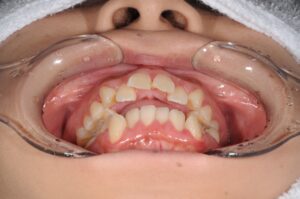

まずは初診時の写真を見て下さい。

【初診時】